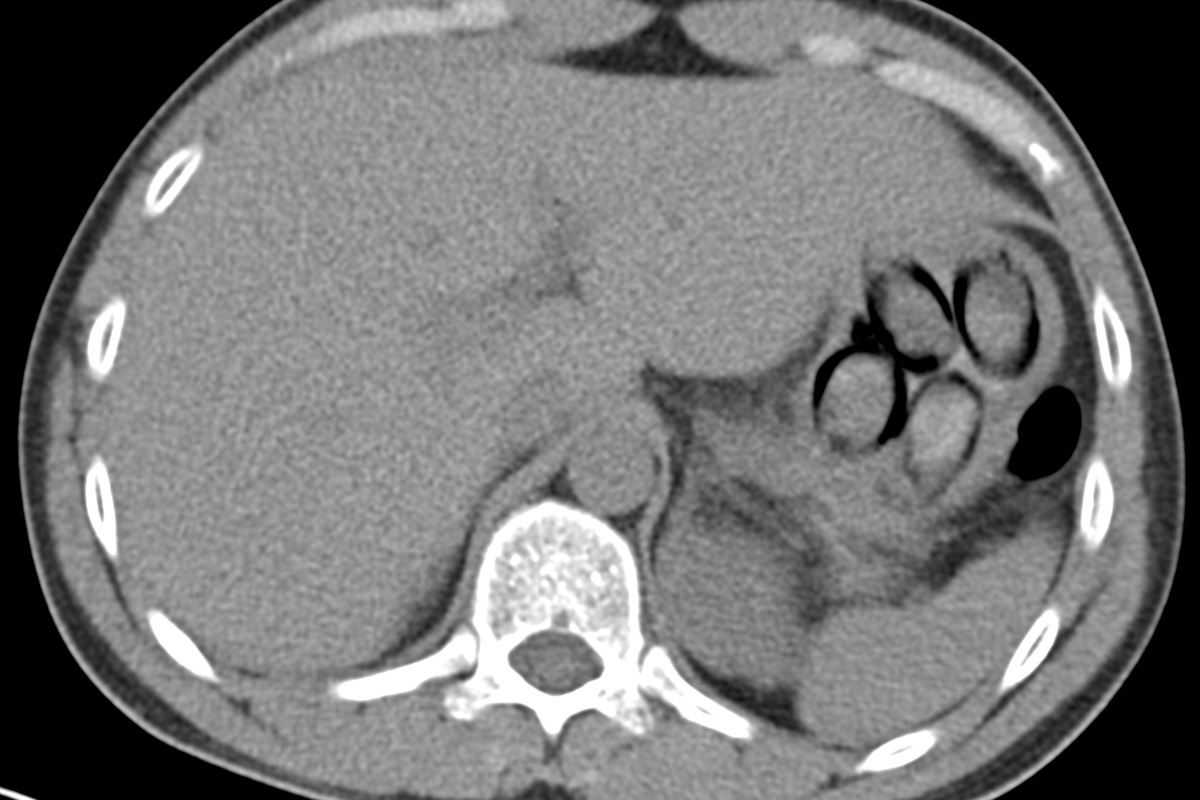

Die Röntgenaufnahme zeigt deutlich die verschluckten Päckchen. (Bildquelle: Hauptzollamt Köln)

Am 04.11.2025 stoppte der Zoll am Flughafen Köln/Bonn (NW) einen Fernbusreisenden aus den Niederlanden. Der 38-Jährige hatte mehr als 100 Gramm Kokain in sogenannten Bodypacks geschluckt. Eine Röntgenaufnahme bestätigte den Verdacht. Die Ermittlungen laufen.

"Die Röntgenaufnahme in einem nahegelegenen Krankenhaus bestätigte letztendlich den Verdacht meiner Kolleginnen und Kollegen, denn im Magen des Mannes waren mehrere Drogenpäckchen klar zu erkennen. Insgesamt schied der Mann dann unter Überwachung sieben sogenannte Bodypacks mit insgesamt mehr als 100 Gramm Kokain aus", so Jens Ahland, Pressesprecher des Hauptzollamts Köln.